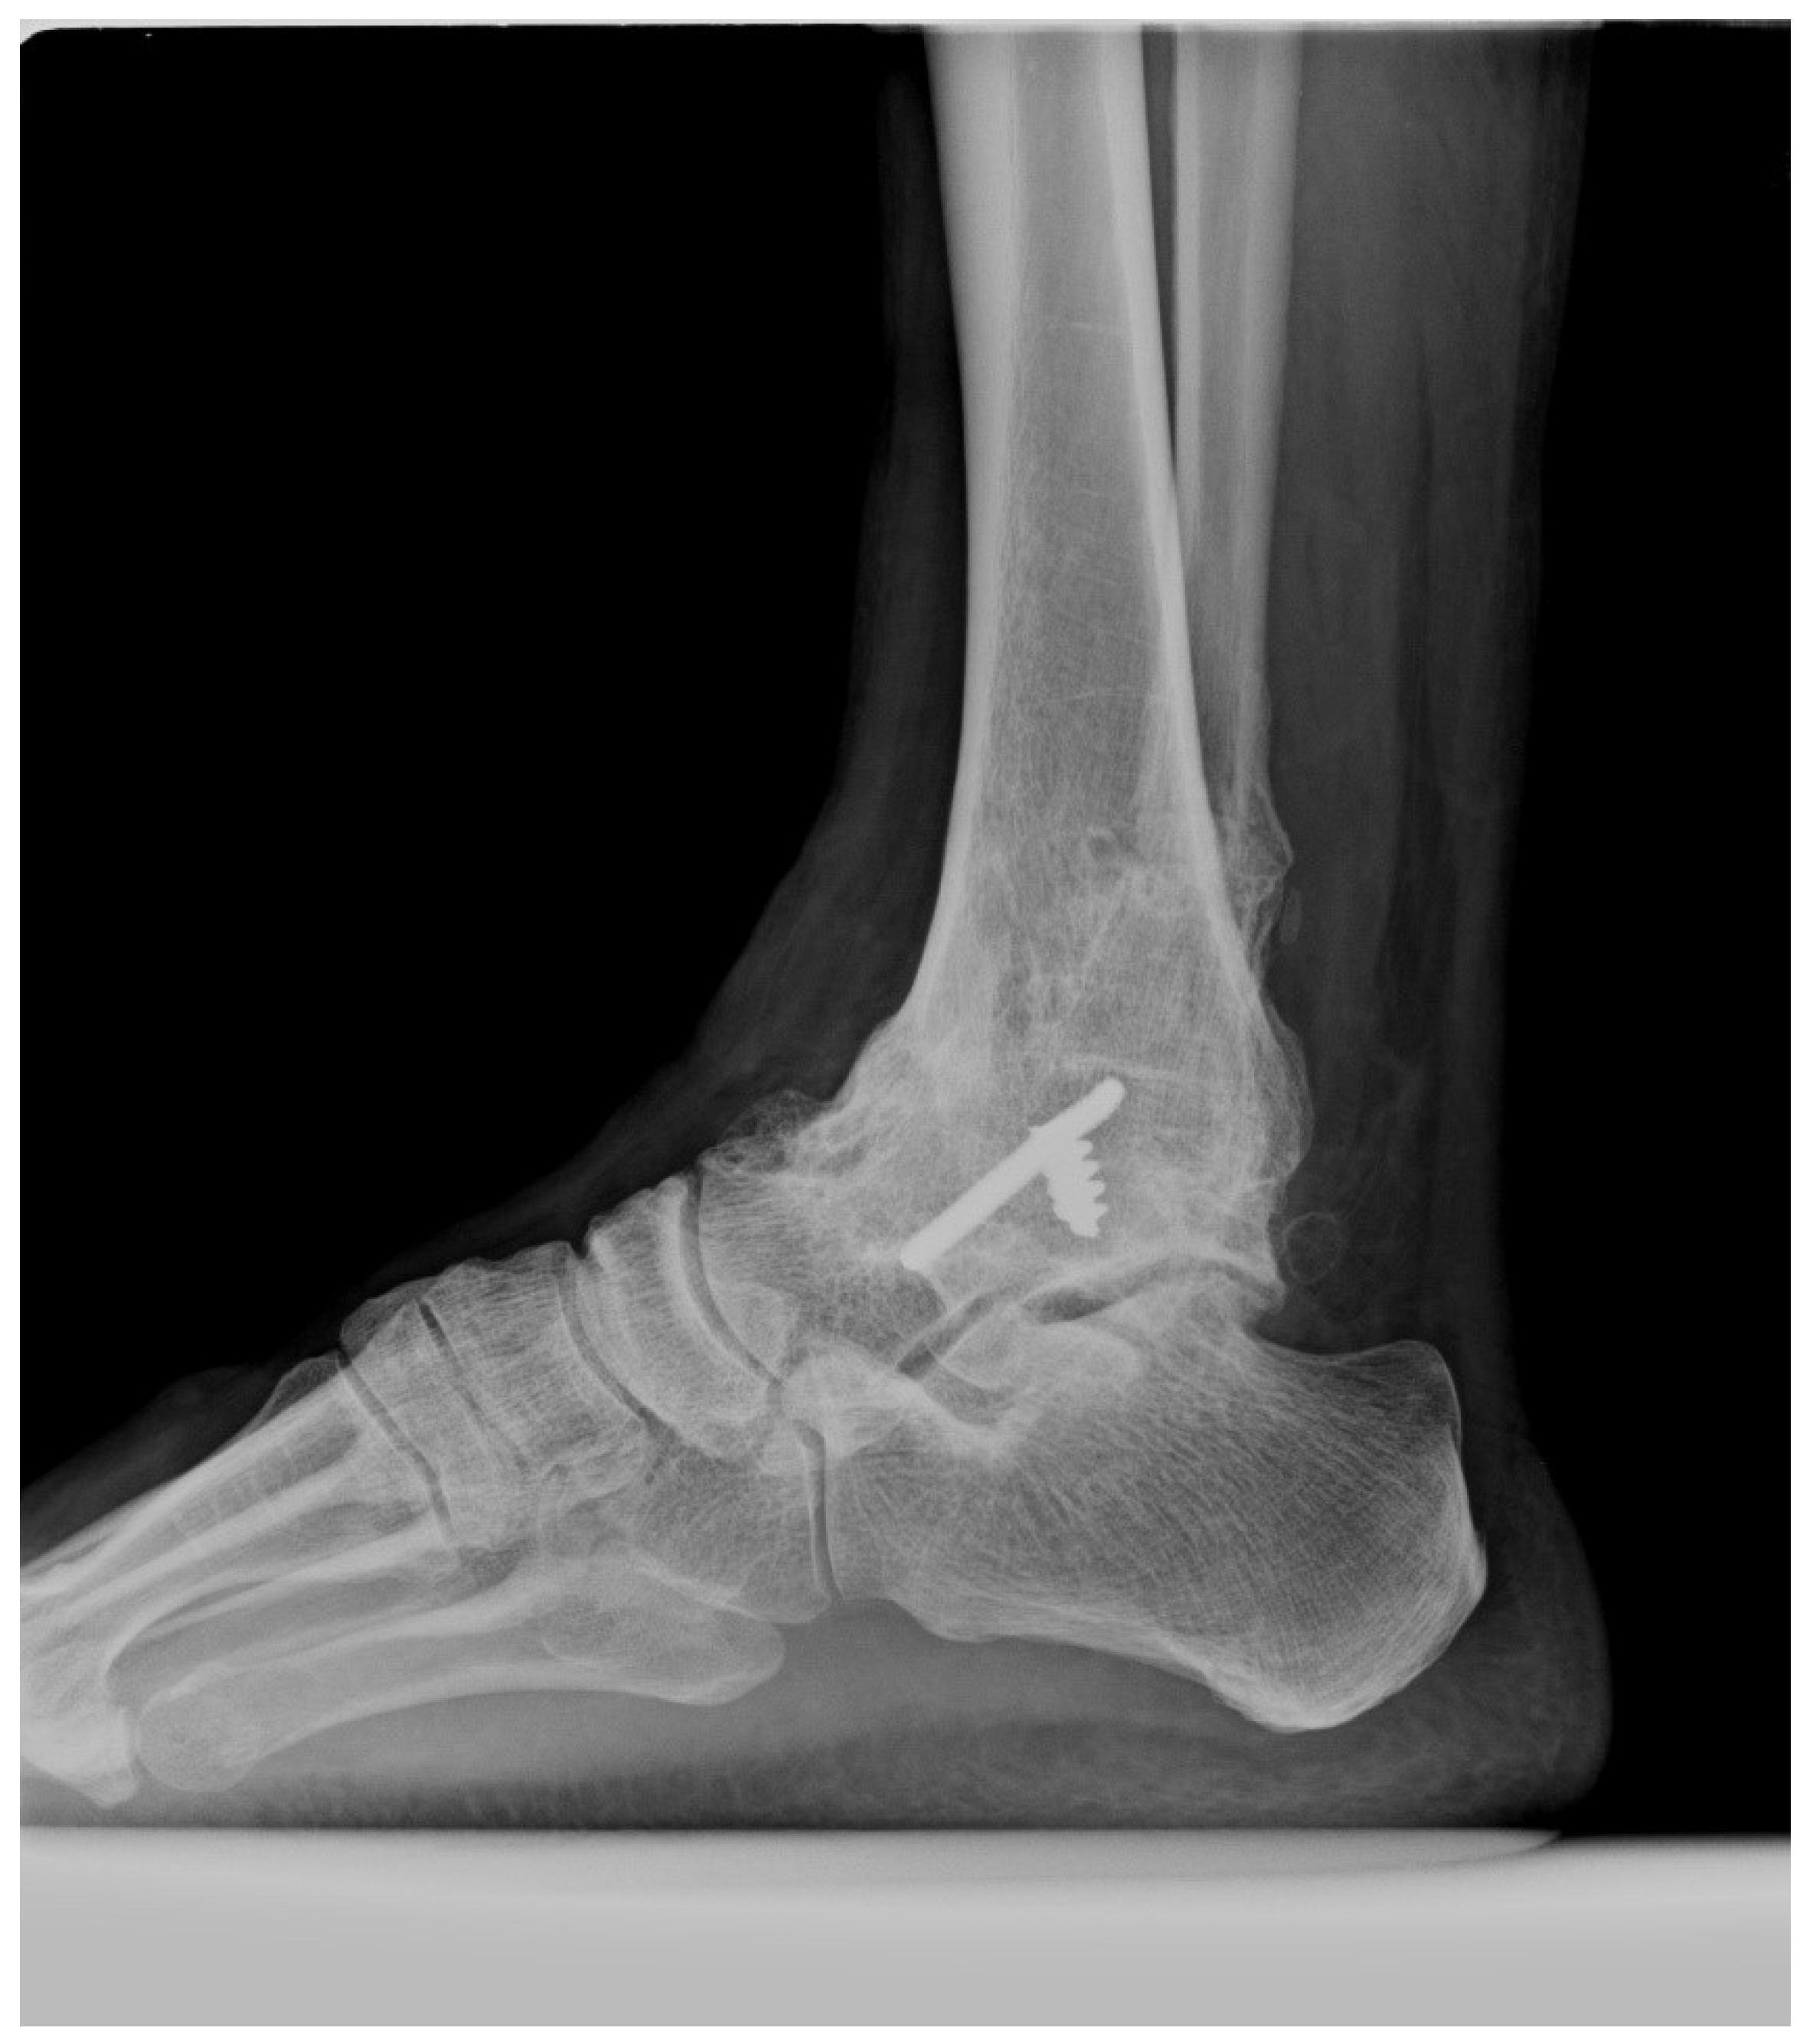

| Diagnosis | Normal ankle–subtalar joint | Isolated fused ankle: 21 Advanced ankle OA: 9 | Isolated fused subtalar joint: 5 Advanced subtalar OA: 25 |